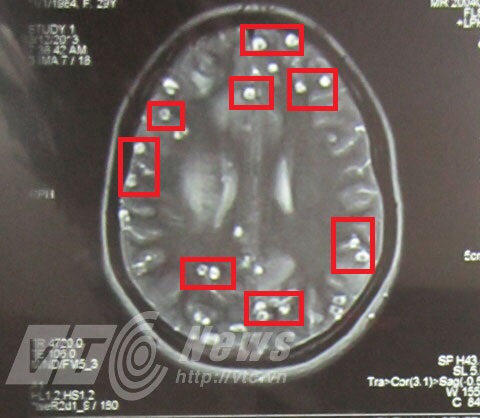

Cho phóng viên VTC News xem phim chụp não của một bệnh nhân bị nhiễm sán lợn, bác sỹ Trần Huy Thọ, Trưởng khoa khám bệnh chuyên ngành, Viện sốt rét – ký sinh trùng – côn trùng TW chỉ từng nang kén sán lợn làm tổ dày đặc trên não.

Những nốt tròn trong có nhân là nang sán lợn làm tổ dày đặc trong não chị H. (Ảnh: BS Thọ cung cấp)

Bác sỹ Thọ nói: Đây là phim chụp của bệnh nhân P.T.H. Bệnh nhân đến khám có triệu chứng co giật, đau đầu, buồn nôn. Chúng tôi chẩn đoán ban đầu bệnh nhân bị ấu trùng sán. Sau khi cho chụp phim, phát hiện rất nhiều nang sán ở trên não. Bệnh nhân ở vùng Bắc Ninh, có thói quen ăn nem thính làm từ thịt nạc sống.